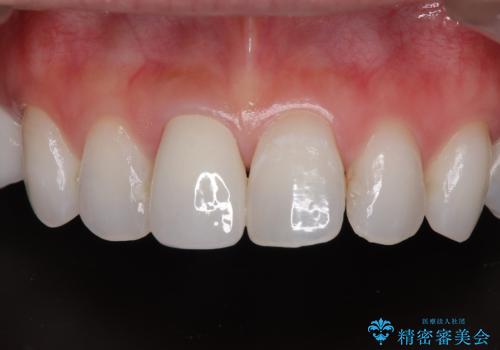

変色を綺麗にしたい 前歯と奥歯のオールセラミッククラウン治療